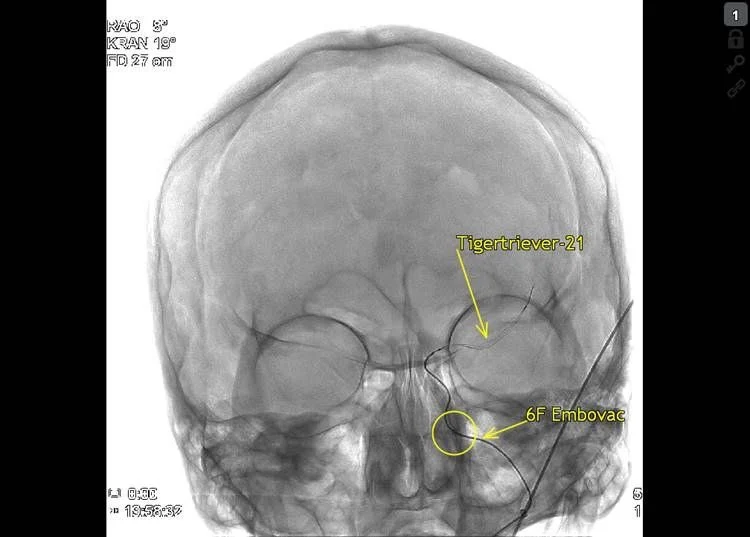

Thrombectomy was done with Embovac and Tigertriever (Rapid Medical) in general anaesthesia (door-to-groin 109 min, 19:44) with first pass recanalization TICI 2c in 16 min (20:00, door-to-final-TICI 123 min).